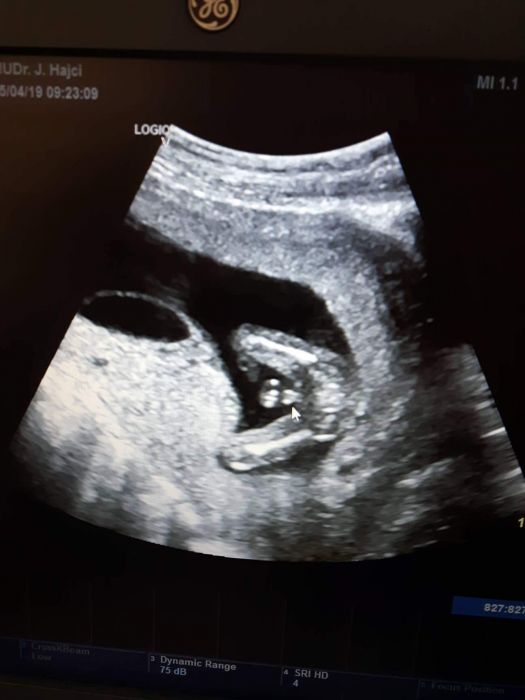

Zdravim maminky, chtela bych Vas poprosit o nazor, jen ze zvedavosti. Poznate pohlavi miminka z ultrazvuku, holka nebo kluk? ? Predem moc dekuji za postrehy ?

Autor: Anička 27.4.2019 v 14:01

[1120591] Kluk.

Autor: Moxha 27.4.2019 v 18:09

Jasný kluk